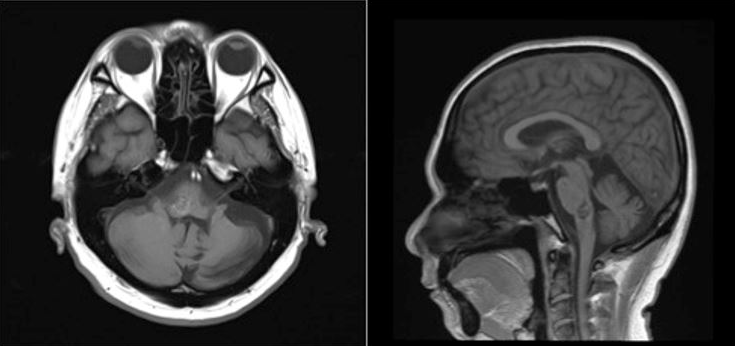

On magnetic resonance imaging, there is a hemorrhage with a complete hemosiderin ring at the level of the pons/ponto-medullary junction, associated with a well-defined lesion with a “popcorn ball” appearance resembling that of a cavernoma (Figure 3 [Fig. 3], Figure 4 [Fig. 4], and Figure 5 [Fig. 5]).

Figure 4: T1-weighted images from the patient’s cranial magnetic resonance imaging

Cavernomas are angiographically occult lesions, which is why conventional T1- and T2-weighted magnetic resonance imaging (MRI) is still being used for its diagnosis [12]. The MRI is able to accurately detect cavernomas, which have a pathognomonic “popcorn-ball” appearance due to loculated hemorrhages, hemosiderin deposition around the primary lesion, and gliotic reaction [12]. Based on imaging, differentials may include hemorrhagic brain metastasis, gliomas, and hemorrhagic telangiectasias (Osler-Weber-Rendu disease) [12].